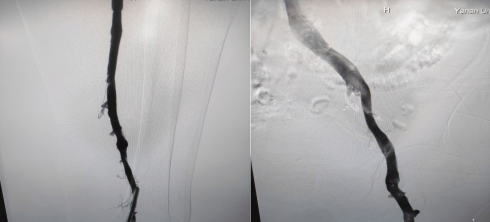

留置接觸性溶栓導管并微量泵人尿激酶溶栓(50萬U/日),小劑量溶栓既降低溶栓出血風險、又保證了療效;溶栓72小時后,拔除溶栓導管,復查造影左下肢深靜脈血流通暢,血栓全部消失,達到預期效果。

復查造影左下肢深靜脈血流通暢,血栓完全消失